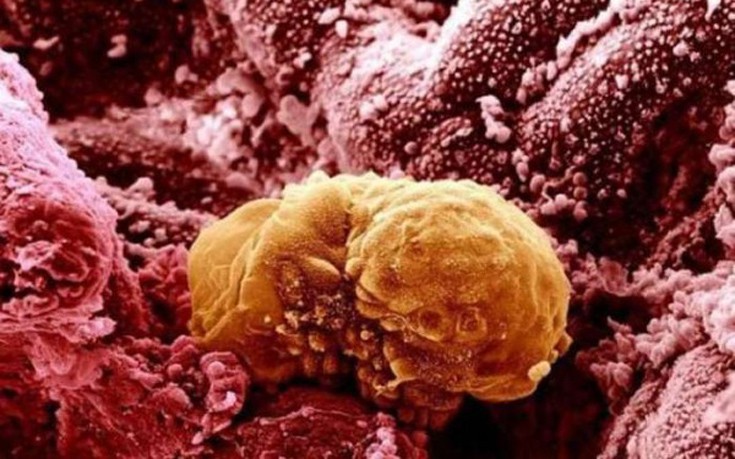

Στο μικροσκόπιο μπορεί να δει κανείς τον κόσμο με μια εντελώς διαφορετική ματιά. Έτσι και το σώμα μας κρύβει λεπτομέρειες και όταν το δει κανείς κάτω από το μικροσκόπιο, δεν μπορεί πάντα να αναγνωρίσει τι βλέπει.

Δείτε παρακάτω μερικά παραδείγματα από όργανα του σώματος ή για παράδειγμα πώς είναι η οδοντική πλάκα…